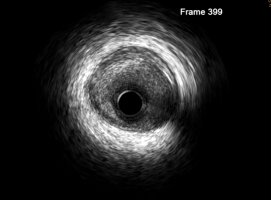

在血管造影检查的基础上,选定所需检查的血管和病变部位,以冠状动脉为例,采用6 F及以上的指引导管放置到冠状动脉口,将0.014英寸的指引导丝送至靶血管的远端,将血管内超声导管沿指引导丝送至需要进行检查的病变部位的远端,一般采用自靶血管的远端至近端以一定的速度连续回撤的方法进行检查,然后对感兴趣的部位再重点检查,自动回撤是进行三维重建所必需的。